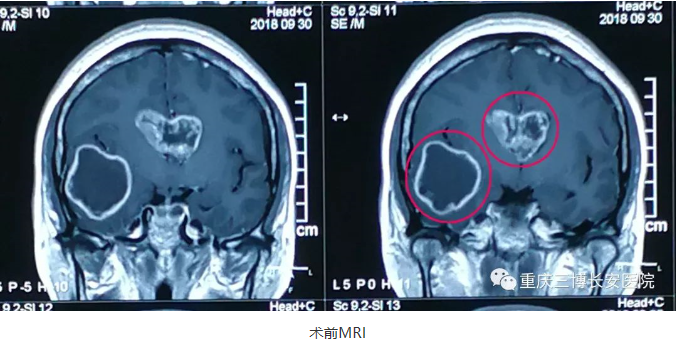

杨某今年40岁,是一位光荣的人民教师,并且是一位班主任,平时工作压力较大,1月前无明显诱因出现头痛,因才开学,工作繁忙,没有太在意,可是随着时间推移,疼痛呈渐进性加重,并伴头昏,恶心。脑部出了问题?不能在拖了,身体要紧。经朋友介绍重庆三博长安医院脑科实力雄厚,共享北京三博脑科专家资源,遂前来就诊,MRI提示:多发性胶质瘤。

NO.2右额颞开颅右颞叶及胼胝体肿瘤切除术

术前,吴斌教授与患者家属进行沟通,详细介绍手术方案、说明手术面临的各种情况及围手术期治疗方案。

打开硬脑膜,见脑压高,术中探查见:右侧颞叶病变,肿瘤组织稀软,质韧,与周围正常脑组织无明显界限,血供中等,病灶呈囊实性,囊液呈黄色,显微镜下肿瘤切除满意,术域彻底止血,继在额部中央前回前方皮层造瘘直达第二处肿瘤,切除胼胝体处肿瘤,肿瘤镜下全切,术域彻底止血。